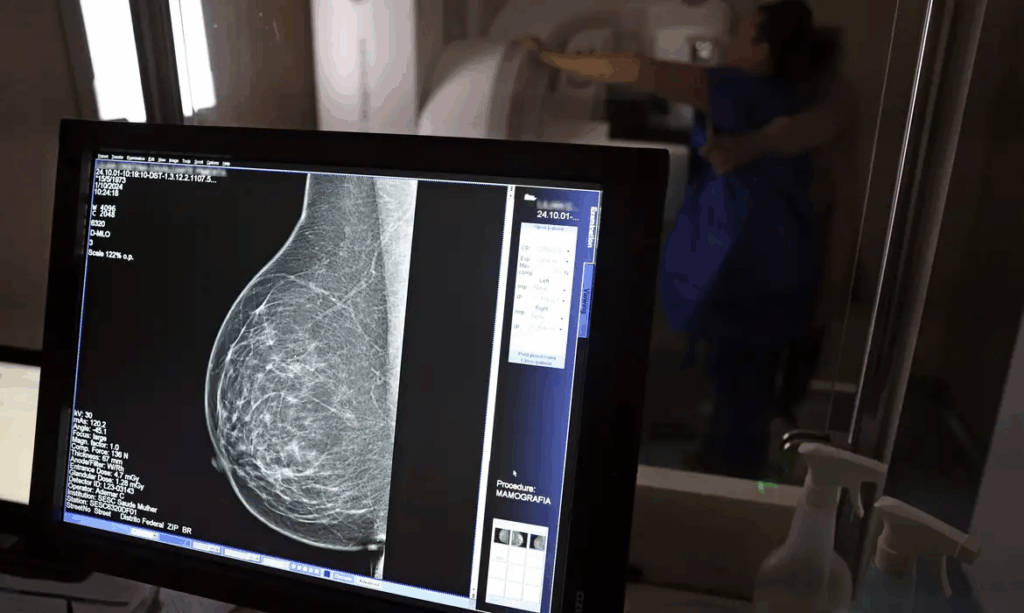

Ministério da Saúde passa a recomendar mamografia a partir dos 40 anos

O Ministério da Saúde passou a recomendar o acesso a mamografia, via Sistema Único de Saúde (SUS), para mulheres de 40 a 49 anos – mesmo que não haja sinais ou sintomas de câncer de mama. De acordo com a pasta, a faixa etária concentra 23% dos casos da doença, e a detecção precoce aumenta as chances de cura.

Até então, a orientação era que o exame fosse feito a partir dos 50 anos.